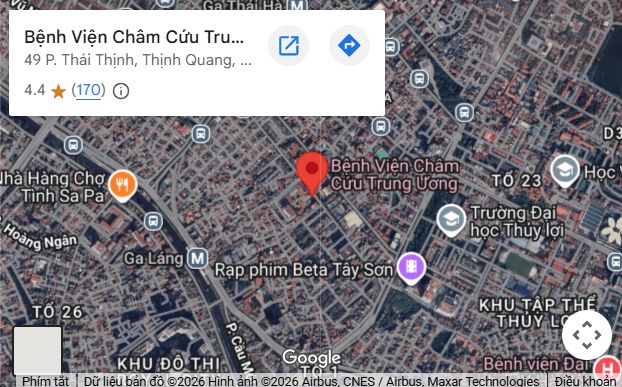

0243 562 4156

Hotline

If you or your relatives are in emergency condition, please contact us at